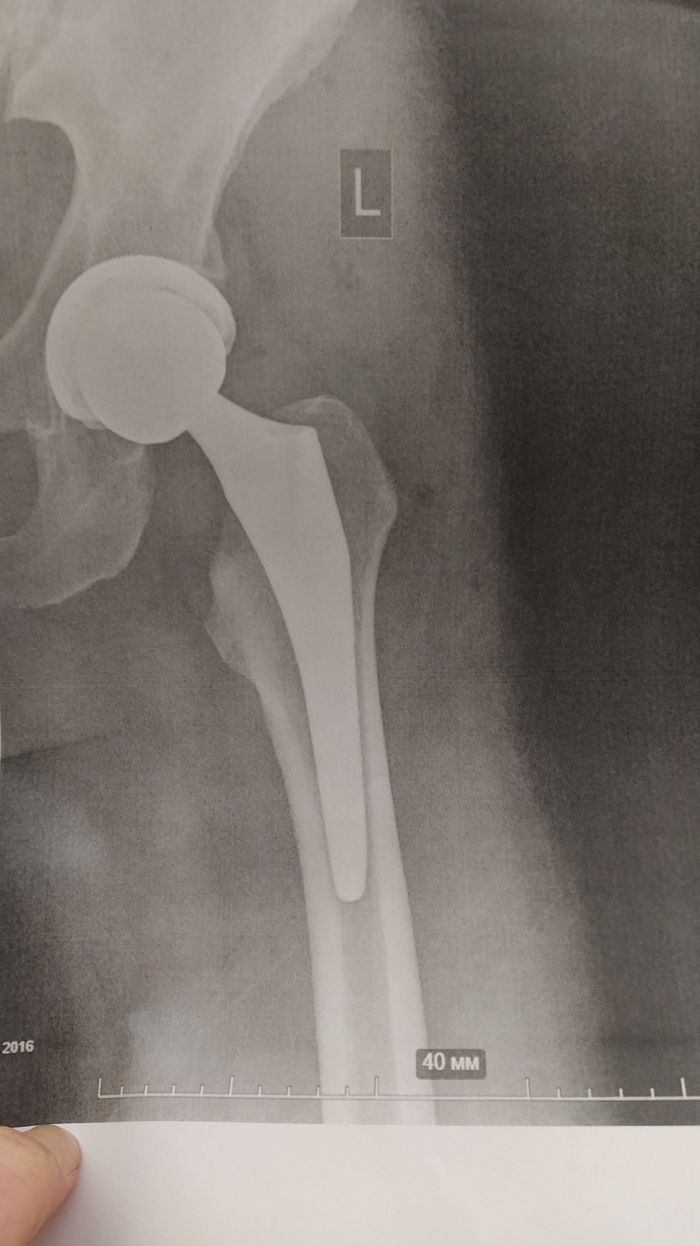

Замена тазобедренного сустава- моя история

Всем привет!

Так уж получилось, что пришлось мне менять тазобедренный сустав. Побочка от приема метипреда, увы. Как обычно, начитавшись историй в интернете, я готовилась к чему-то не особо трэшовому, особенно, на фоне пережитых мной ранее операций.

1-го февраля я легла в институт Поленова (он же теперь Алмазова), куда не так давно перевели отделение травматологии. Рассчитывала, что операция будет на следующий день, но как обычно - это не мой вариант. То не было инструментов, то не хватило пакета крови на всякий пожарный, то Луна в Меркурии. В итоге на операцию меня отправили аж 4-го числа.